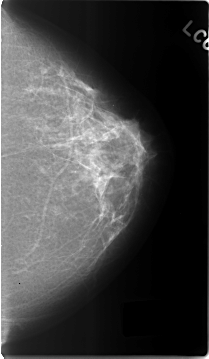

Volume: benign_04 Case: C-0302-1

C_0302_1.LEFT_MLO

C_0302_1.LEFT_CC

DATE_OF_STUDY 27 3 1995

PATIENT_AGE 46

DENSITY 2

LEFT_CC LINES 4656 PIXELS_PER_LINE 2712 BITS_PER_PIXEL 12 RESOLUTION 50 NON_OVERLAY

LEFT_MLO LINES 4592 PIXELS_PER_LINE 2736 BITS_PER_PIXEL 12 RESOLUTION 50 NON_OVERLAY

ABNORMALITY 2

LESION_TYPE CALCIFICATION TYPE PLEOMORPHIC DISTRIBUTION CLUSTERED

ASSESSMENT 3

SUBTLETY 2

PATHOLOGY BENIGN

LESION_TYPE MASS SHAPE OVAL MARGINS OBSCURED

SUBTLETY 5